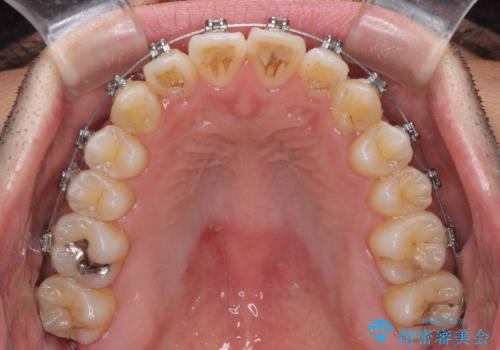

左右の八重歯が気になる ワイヤー装置での咬み合わせ改善

- 八重歯と前歯のデコボコを気にして来院された患者様です。

営業職であり、商談などで飲食をする機会が多いとのことで、インビザラインではなく、ワイヤー装置にて矯正治療を行うこととしました。